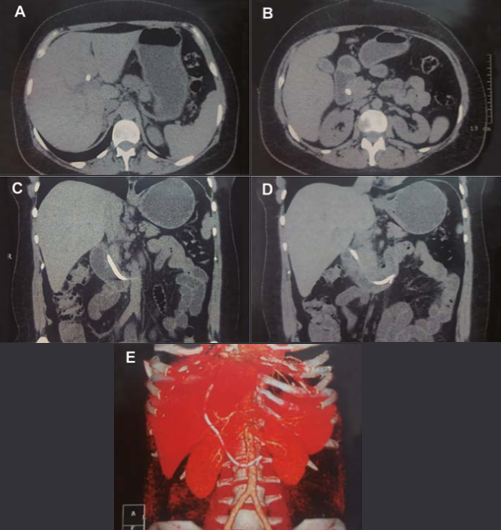

A stent was inserted in the biliary tract. An abdominal computed tomography (CT) scan revealed intrahepatic biliary ducts dilation, a hypodense gallbladder with parietal calcifications that may correspond to porcelain gallbladder suggestive of cholangiocarcinoma. (Figure 2 A-E).